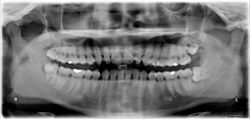

ضرس العقل، أو الضرس الثالث، هو ضرس يقع في أخر الفك، وهو آخر ما ينشأ من الأسنان في الإنسان. ويوجد ضرس عقل واحد في كل ركن من أركان الفم. ويبدأ في الظهور ما بين سن 17 و25.[1] Most adults have four wisdom teeth, but it is possible to have more—in which case they are called supernumerary teeth—or fewer—a condition called hypodontia. ويؤثر نمو ضرس العقل على باقي الأسنان، أو قد يسبب "إعوجاجهم".[2] وعادة ما يتم خلع ضرس العقل عندما يعاني المريض من بعض المشكلات.